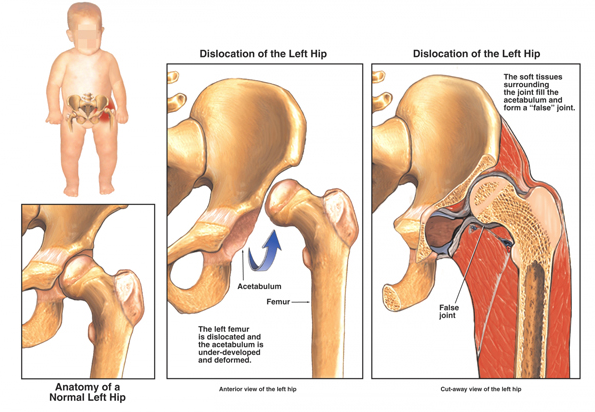

5. Babas wat gebore word met ‘n heupgewrig wat maklik uit die potjie kan glip, word in ‘n ‘padda’-spalkie geplaas sodat die heuppotjie reg kan ontwikkel om die kop van die bobeen in die potjie te anker.

6. Lees meer oor heup ontwrigting: https://www.mayoclinic.org/diseases-conditions/hip-dysplasia/symptoms-causes/syc-20350209